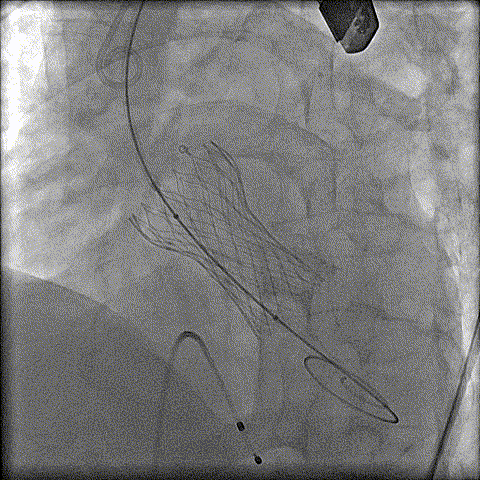

预扩

猪尾中部释放

稳定回收

评估

最终释放

后扩

无瓣周漏